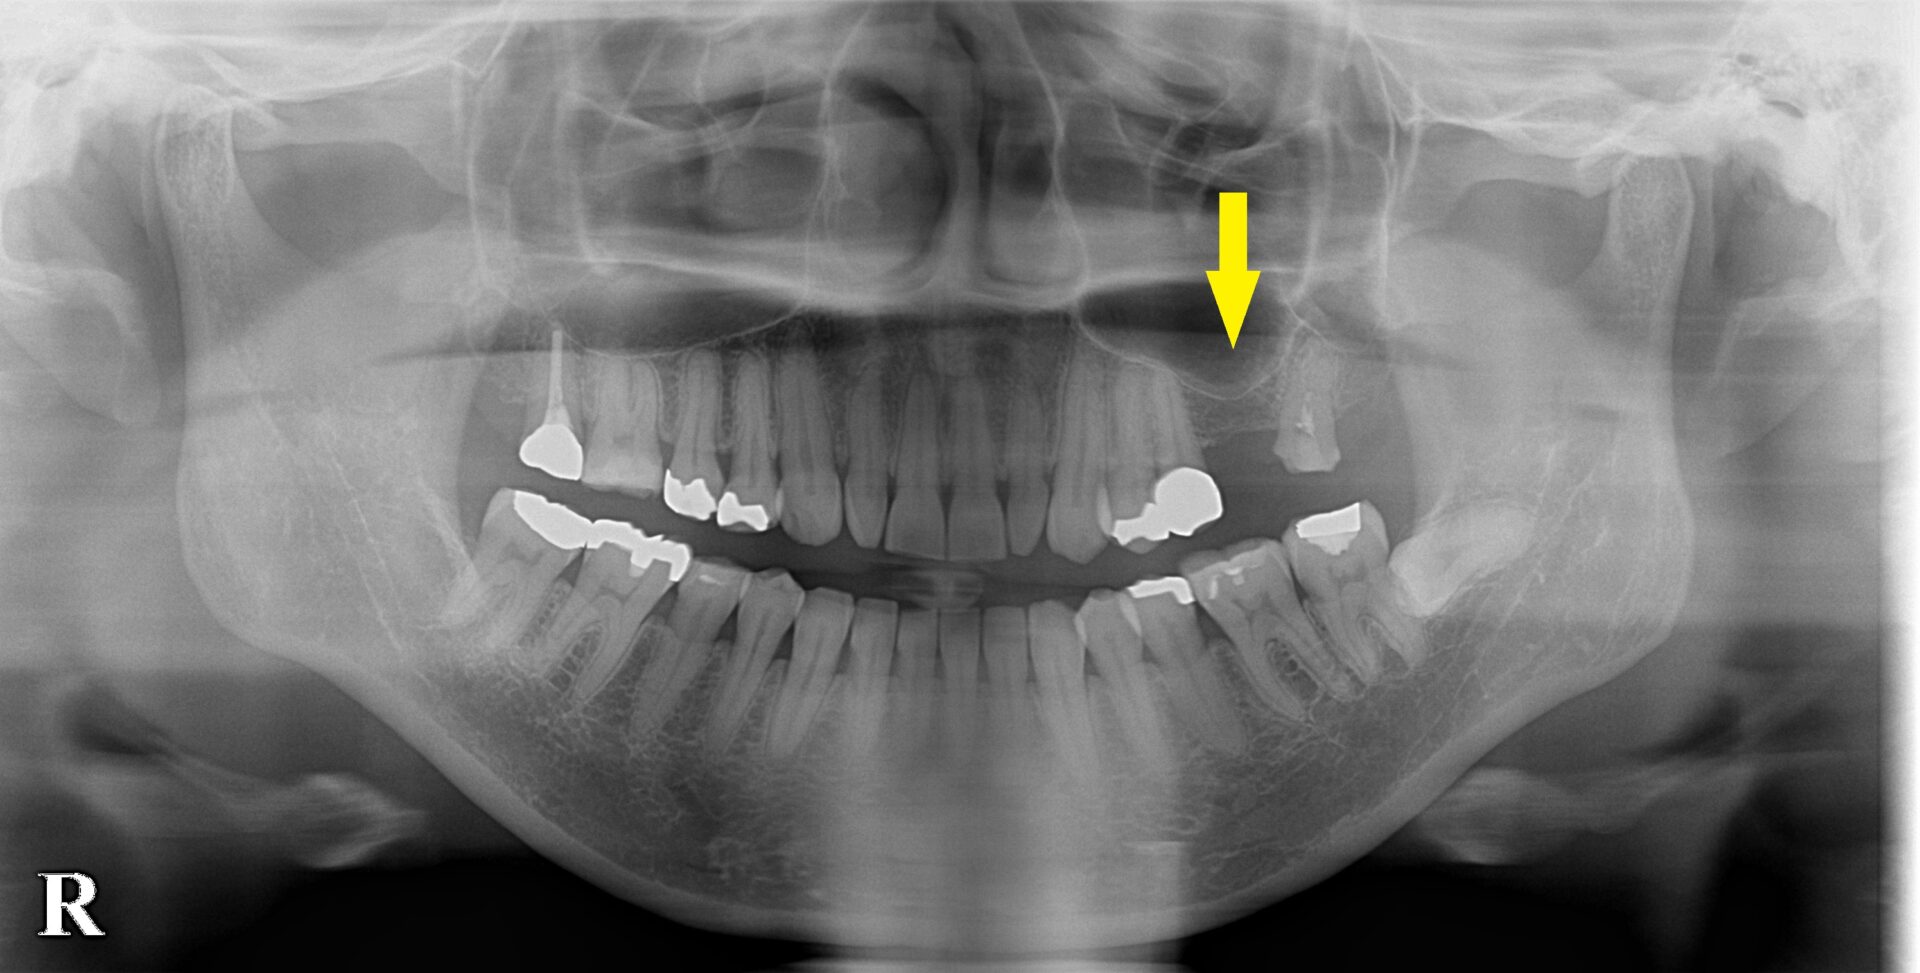

CTを撮影してみると、方向によっては、骨がありそうに見えますが、やはり十分な骨量とはいえませんでした。

ある程度の骨はありますので、ワイドインプラントを用いて、人工骨は使用せず、骨造成も行わないで、インプランント埋入が可能であると説明させていただきました。

ご納得いただけましたので、本日、ワイドショートインプラント、直径5.0mm、長さ7mmのインプラントを埋入しました。

下の写真、2段目が手術前のCT、3段目が手術後のCTです。